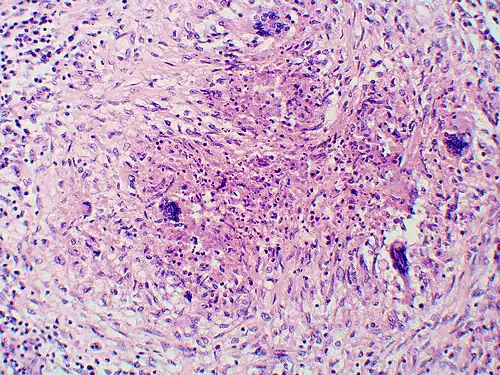

-

Granuloma with early suppuration. The fungal organisms are difficult to recognize at this low magnification. -

Large yeast-like fungi seen within giant cells at arrows. -

Large yeast-like fungi seen within giant cells at arrows. Budding yeasts in the cytoplasm of giant cells at the arrows. Broad-based budding and double-contoured cell walls are seen in the giant cell in the center are characteristic of Blastomyces dermatitidis. -